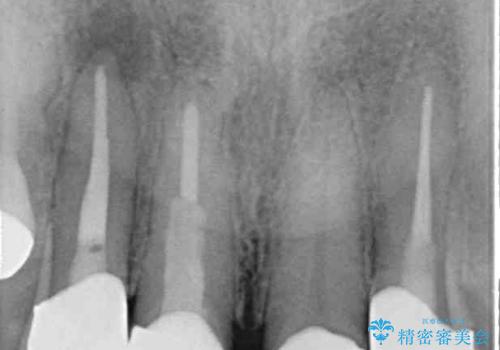

ブリッジの支台歯は2本とも神経を取り除いている歯であるため、咬合力の強い方ですと、支台歯も歯根破折をするリスクがあります。

今回はそれほど咬合力が強いとは思われなかったため、ブリッジによる補綴治療を行いましたが、念のため、就寝時にはナイトガードとしてマウスピースを装着するようお願いしました。